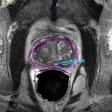

Can AI help to improve radiologist accuracy in prostate MRI?